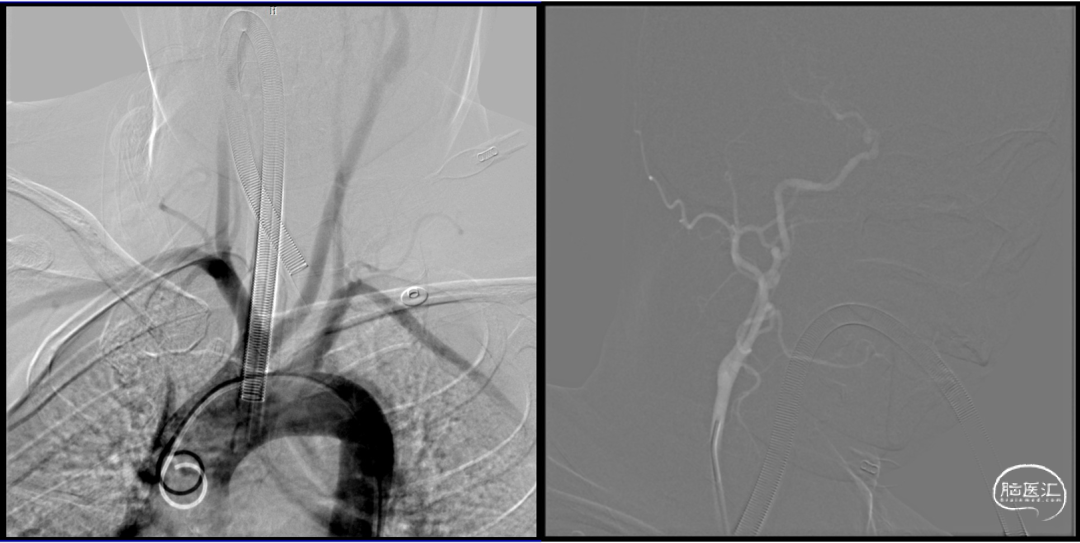

通路:

右股A 8F鞘+ 8F Neuron MAX +通桥颅内支持导管TGC055-05-125,左股A 6F鞘+强生6F Envoy DA 指引管;

微导丝:

Synchro-10、Mirage0.008微导丝。

微导管:

马拉松微导管;

液体栓塞材料:

Glubran2胶。

球囊:

HyperGlide 4mm*20mm封堵球囊。

微导管超选

球囊保护下微导管造影证实假性动脉瘤

球囊保护下25%gb栓塞